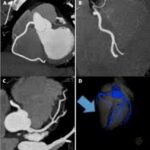

Cardiac CT Angiography works through the use of X-ray technology and contrast dye to provide detailed images of the heart’s blood vessels. Contrast dye is first injected into a vein, which helps outline the coronary arteries in the images. The CT scanner takes several X-ray images from many different directions; a computer processes the images into a 3-D image of the heart. This enables the doctors to trace blockage, narrowing, or any other defects in the coronary arteries. This non-invasive procedure provides useful information for diagnosing coronary artery disease, heart aneurysms, and other heart conditions that generally take a few minutes to complete.